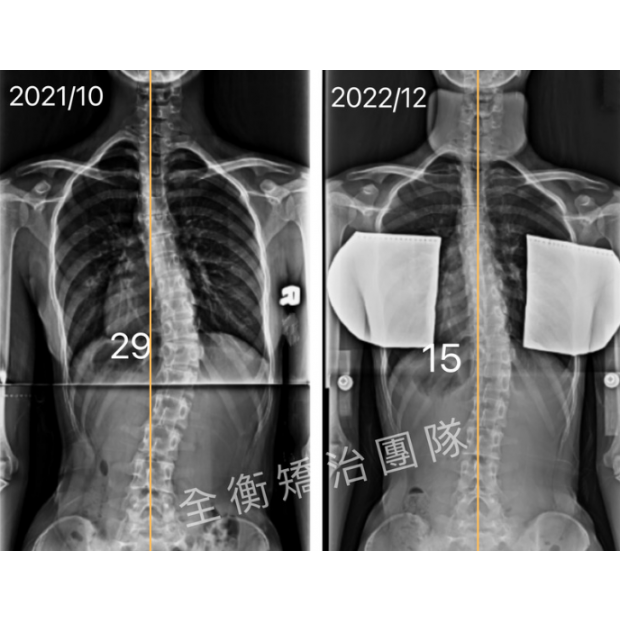

16歲女生,青春期末期才發現側彎,還有機會嗎?16歲女生,青春期末期才發現側彎,還有機會嗎?

16歲妹妹,高一健檢才發現脊椎側彎

經過一年的復健和追蹤

側彎角度由29度進步至15度,減少50%!

旋轉也從12度減少到6度 -